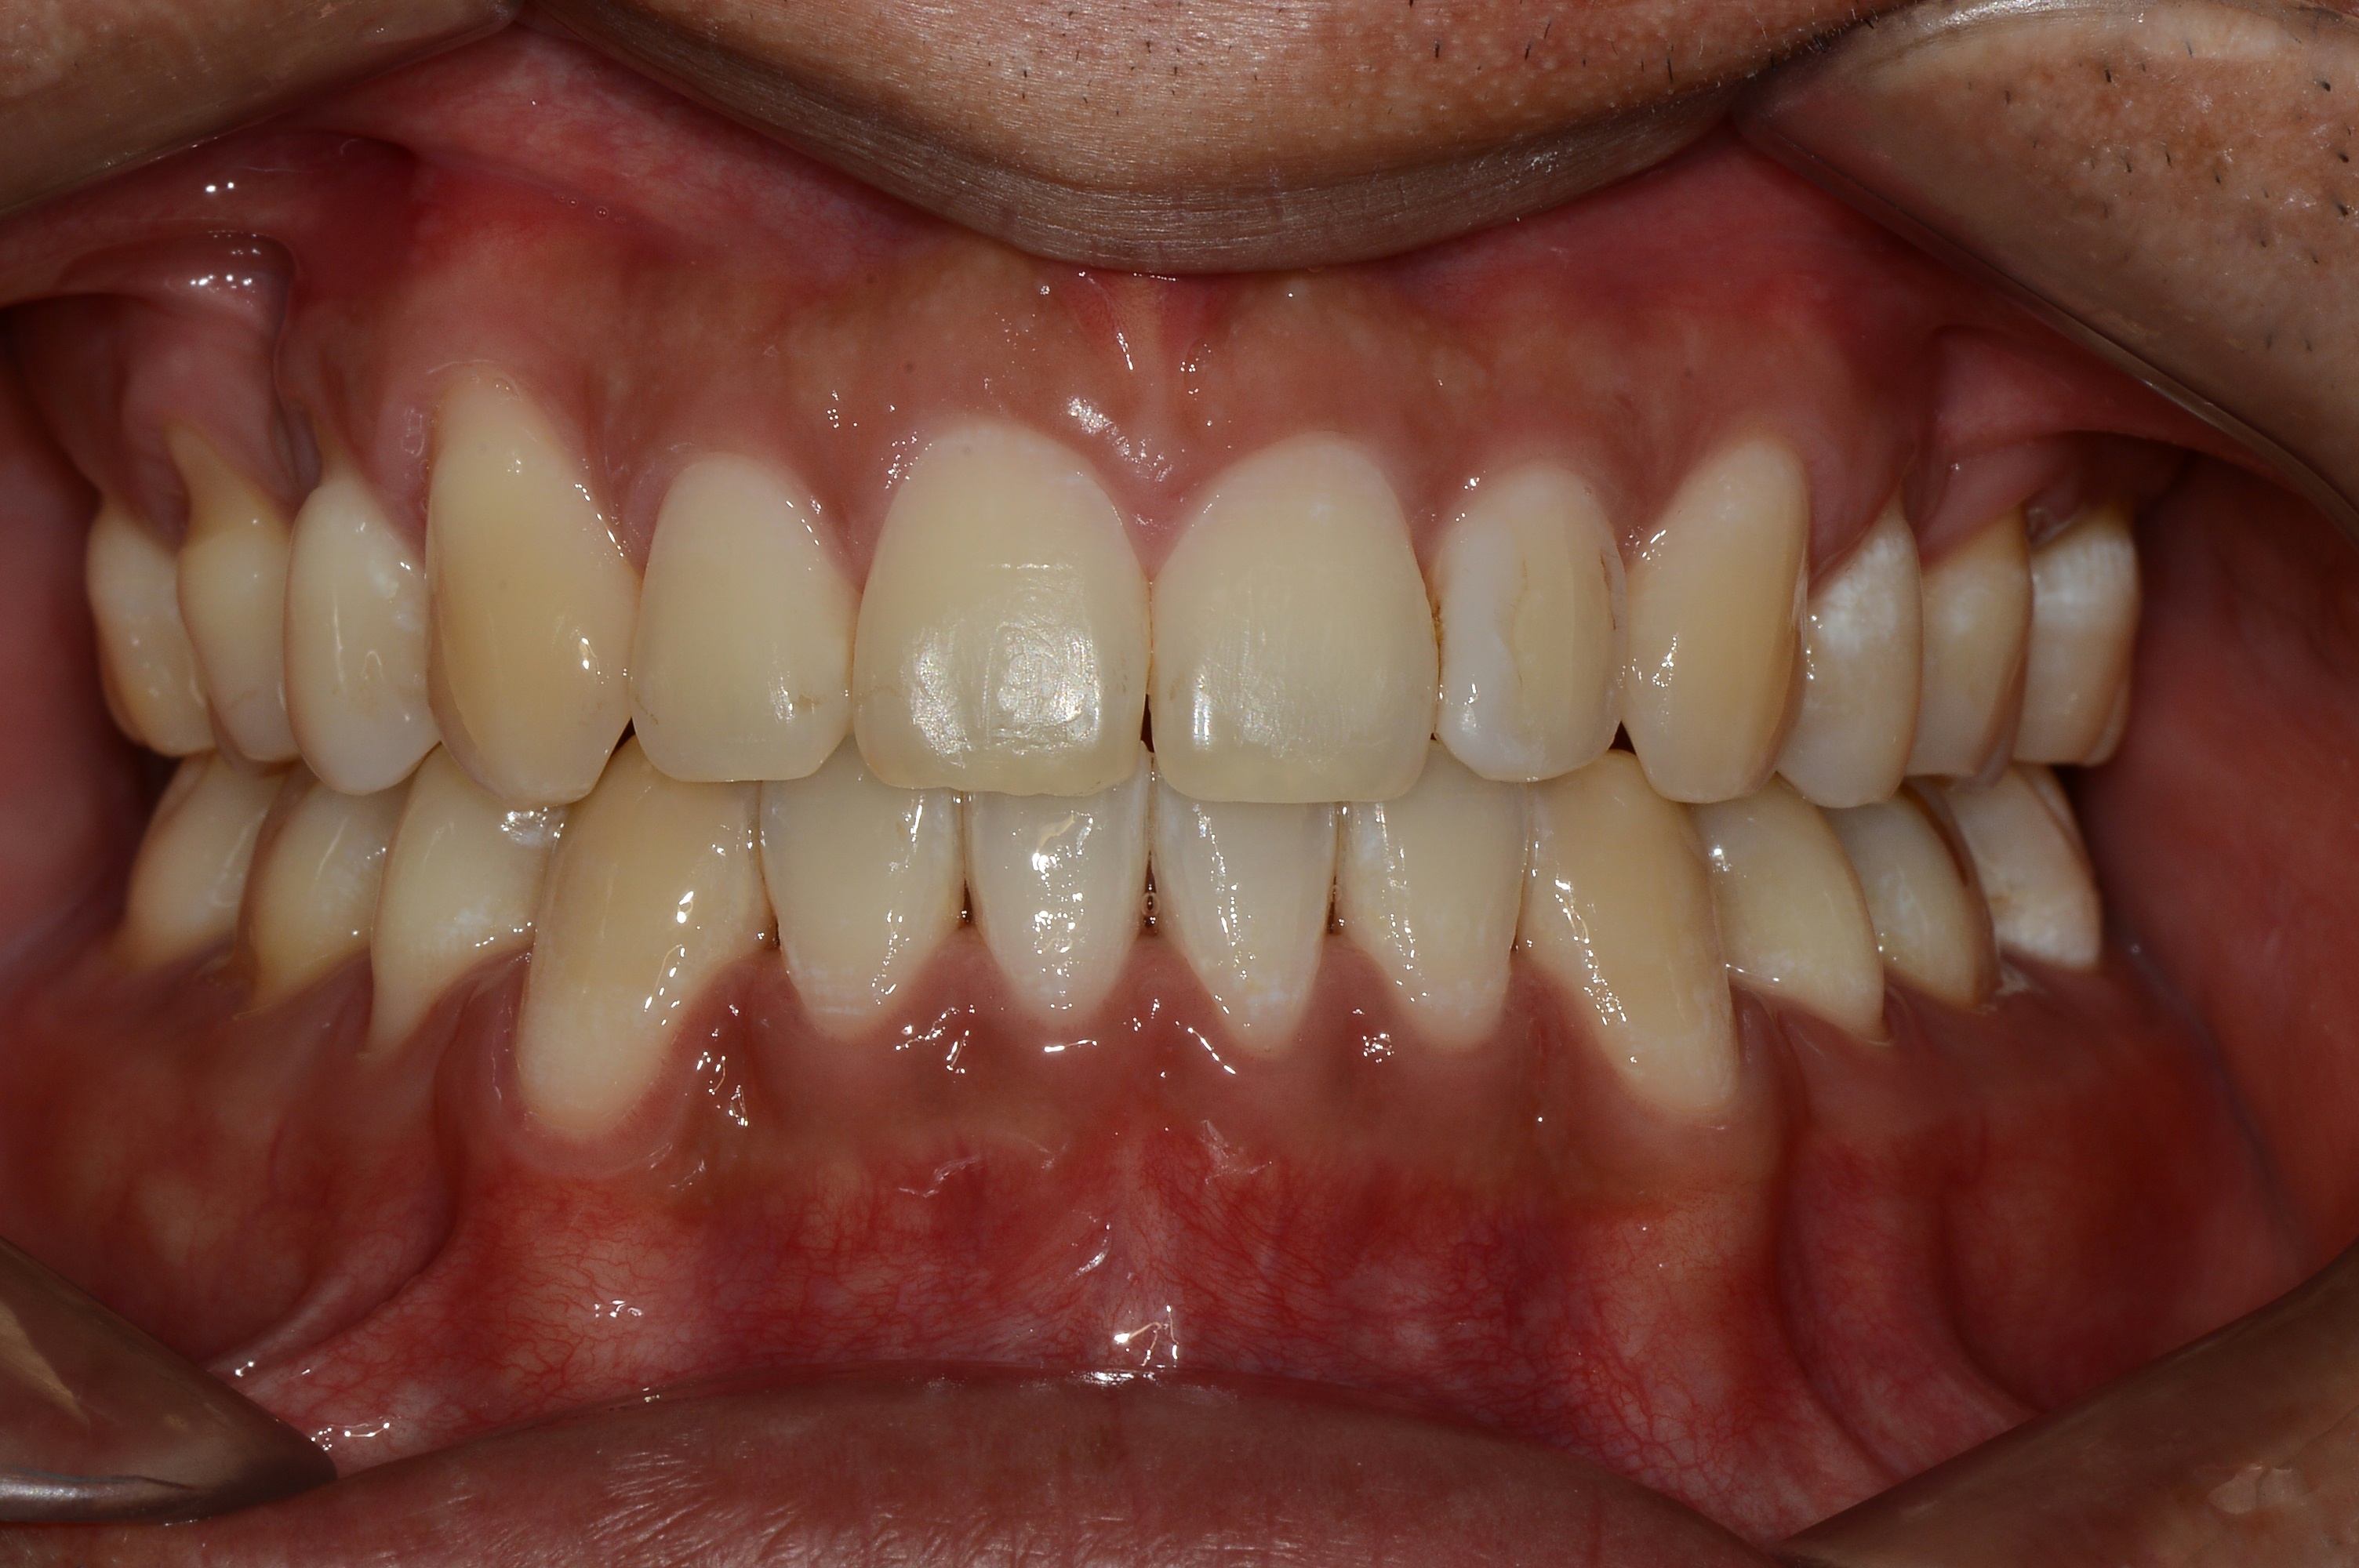

치료 후 사진입니다.